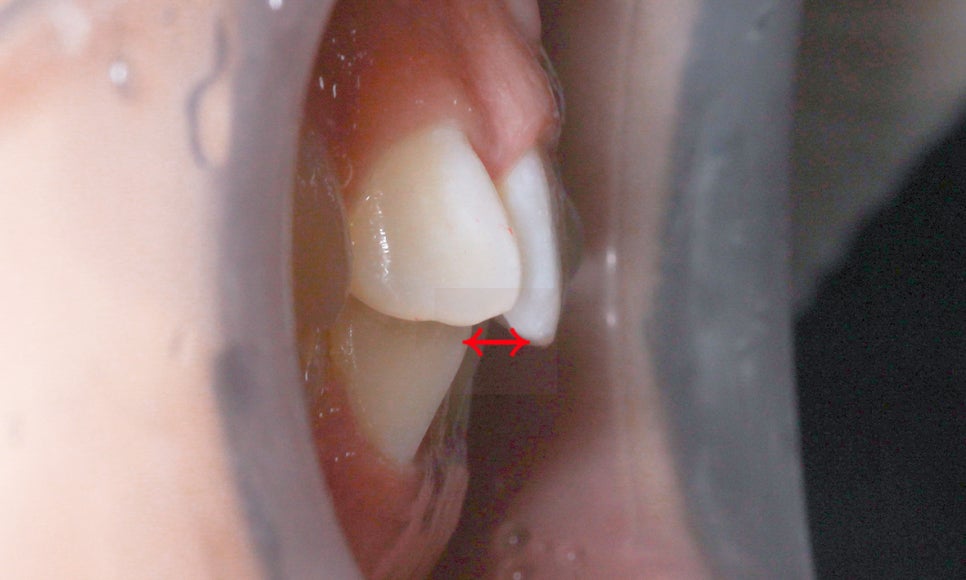

상악 전치부의 치아 배열을 확인하면

위처럼 중절치가 설측으로 미세하게 뻐드러져 있고

측절치의 각도는 대략 90도 정도로 틀어진 모습인데요,

위와 같은 case의 경우 1급 부정교합에

해당하거나 혹은 부정교합 증상 없이

몇 개의 치아만 회전되어 있다면 (앞니틀어짐)

문제가 있는 치아들을 부분적으로

교정할 수 있습니다.